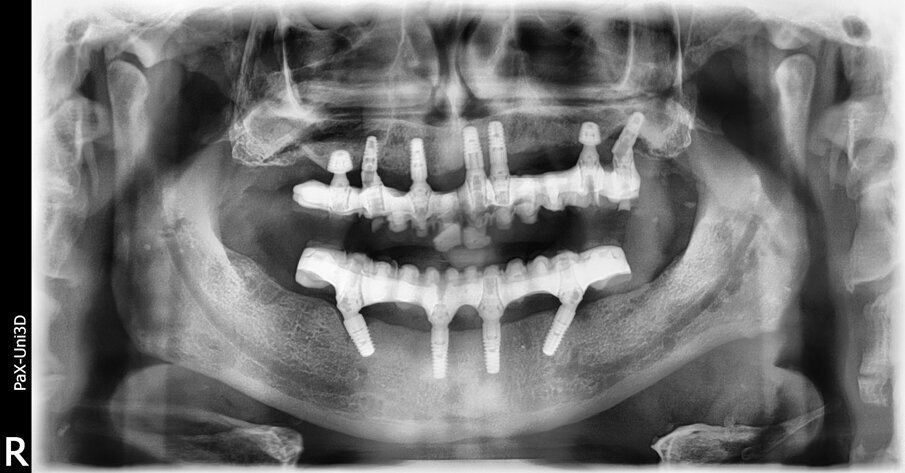

Il follow up è stato programmato con cadenza semestrale. Al momento della produzione di questo articolo, il caso è stato seguito per 18 mesi. Nell’arco di questo periodo è stata segnalata solo una complicanza di minore entità. La rottura di un angolo incisale dell’incisivo centrale, che è stata riparata direttamente alla poltrona. Dopo 18 mesi, l’ortopanoramica di controllo evidenzia una perfetta stabilità e, anzi, un miglioramento dei livelli ossei perimplantari. In particolare, a livello degli impianti ultra-short è possibile apprezzare una migliore densità ossea circonferenzialmente all’impianto e persino nella sua porzione più coronale, come è possibile apprezzare confrontando l’ortopanoramica eseguita immediatamente dopo l’intervento con quella a 18 mesi (Figg. 11a, 11b).

Fig. 11a_Ortopanoramica a 18 mesi. Appare evidente l’incremento della densità ossea intorno agli impianti, in particolare di quelli ultra-short.

Fig. 11b_Confronto della qualità ossea prima e dopo 18 mesi degli impianti ultra-short inseriti a livello del mascellare superiore destro e sinistro.